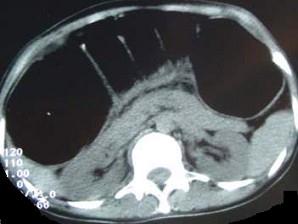

问题 女,30岁,便秘、腹痛腹胀多年,CT检查如图,最可能的诊断是 ( )

选项 A、结肠肠扭转 B、结肠肠栓塞 C、先天性巨结肠 D、结肠肠套叠 E、结肠肠梗阻

答案 C